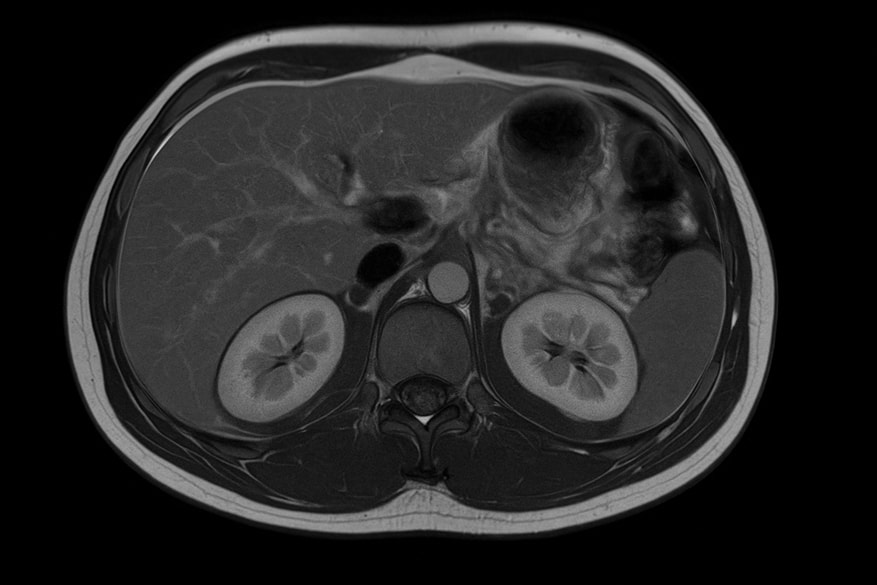

МРТ надпочечников с контрастом — современный метод лучевой диагностики. Он позволяет с высокой точностью изучить внутреннюю структуру и функции надпочечников.

Магнитно-резонансная томография надпочечников с контрастом применяется для оценки строения тканей, состояния сосудов и обнаружения скрытых изменений, сопровождающих эндокринные заболевания. После введения препарата специалист видит мельчайшие сосуды и участки измененного кровоснабжения, что помогает выявить патологию и уточнить структуру новообразования.

Методика информативна при гиперплазии надпочечников, кистозных образованиях и аденомы надпочечников, особенно когда другие виды визуализации дают неполные данные. Высокопольный аппарат томографа формирует четкий снимок, а применение контрастных веществ последнего поколения гарантирует точность и безопасность процедуры.

Исследование проходит в два этапа. На первом выполняется стандартное сканирование без контраста в режимах T1-, T2- и STIR-взвешенных изображений. Эти данные позволяют оценить анатомию органов, плотность тканей и симметрию желез. Второй этап — дополнительное контрастирование, когда в вену вводится препарат на основе гадолиния. Контраст циркулирует по кровеносной системе, обеспечивая различимую визуализацию сосудистого рисунка и структурных особенностей надпочечников.

Контрастное усиление позволяет не только уточнить структуру новообразования, но и зафиксировать динамику его накопления и выведения препарата. При злокачественных опухолях отмечается быстрый захват контраста и столь же стремительное его вымывание, тогда как доброкачественные опухоли характеризуются медленным и равномерным распределением вещества. Такой анализ называется динамическим перфузионным картированием и входит в стандарт современных МР-протоколов.

После завершения процедуры врач анализирует изображения, оценивая форму, размеры и плотность тканей. МРТ надпочечников с контрастом помогает определить структуру новообразования, сосудистую активность и наличие метастазов. При контрастном усилении отчетливо видны отличия между доброкачественными опухолями и злокачественными.